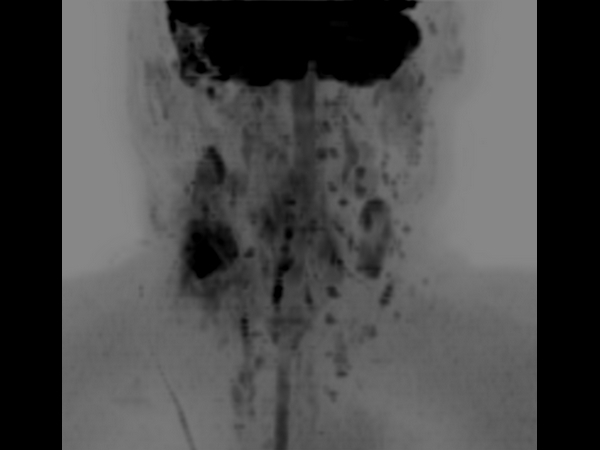

DWIBS (b700) - Coronal MIP